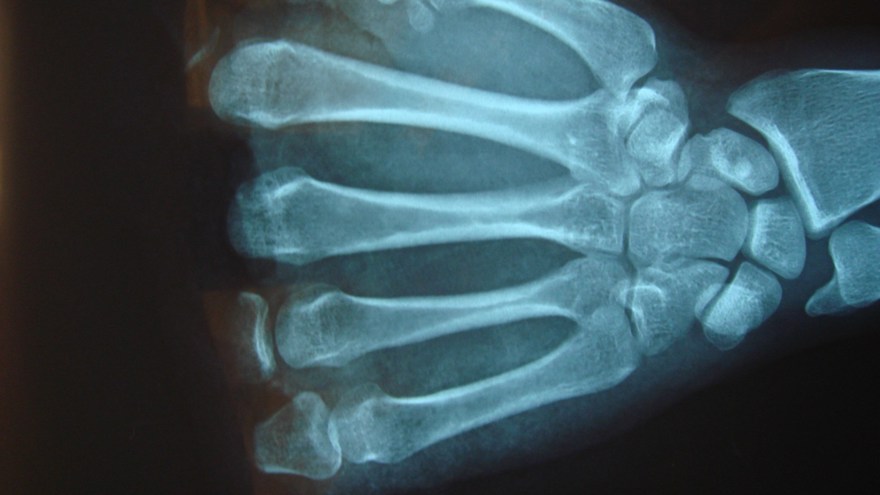

SR, CRP, leukocyt antal och andra prover ger också svag och sen indikation då den lokala infektionen endast ger svag allmän inflammation i kroppen. Diagnosen ställs istället via röntgenbildernas utseende. Ofta får röntgen undersökningen upprepas och man ser då suddigt avgränsade mörka områden som ibland kantas av en periostal reaktion.

Det tar vanligen 2-3 veckor för att röntgenförändringarna att utvecklas. En snabbare och tydligare diagnos kan man få genom MR eller Leukocyt scintigrafi men de ger dålig information efter trauma.